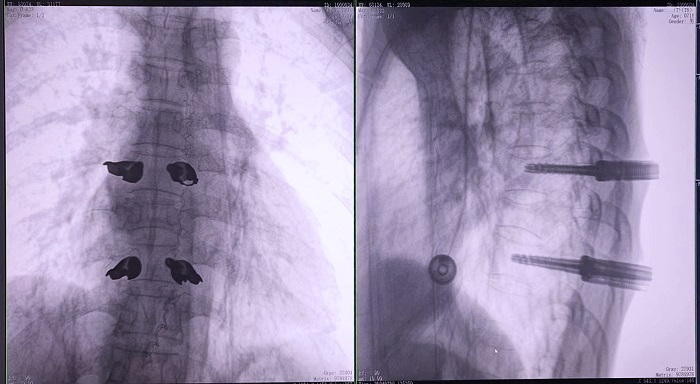

患者:71歲,男性,胸8椎體壓縮性骨折

術(shù)式:機(jī)器人輔助經(jīng)皮釘棒系統(tǒng)復(fù)位內(nèi)固定手術(shù)

普愛醫(yī)療骨科手術(shù)機(jī)器人的高精度機(jī)械臂,按照規(guī)劃好的路徑及角度,自動(dòng)精準(zhǔn)定位穿刺點(diǎn),醫(yī)生打入克氏針后,正側(cè)位圖像顯示精度滿足預(yù)期,醫(yī)生完成置釘?shù)群罄m(xù)手術(shù)操作。